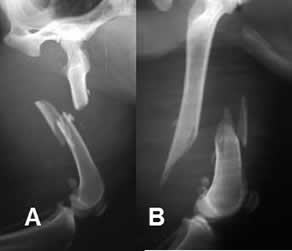

Fig 47. Fractura diastasada.

A: y B: Rx lateral. Fracturas conminutas, rotadas y diastasadas en las diáfisis femorales.